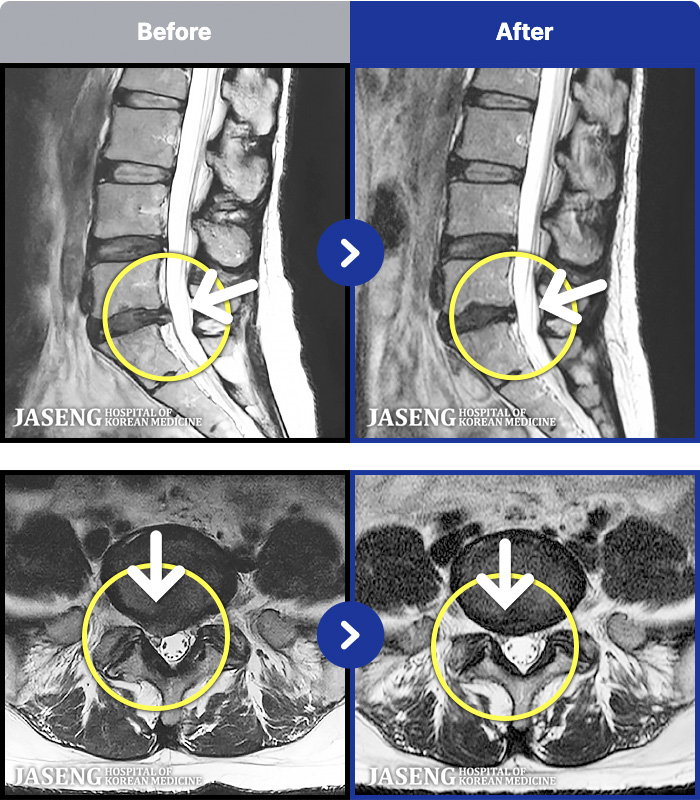

1,286 MRI ũ ʸ Ȯϼ.

[ϻ] 24.07.25~25.08.01